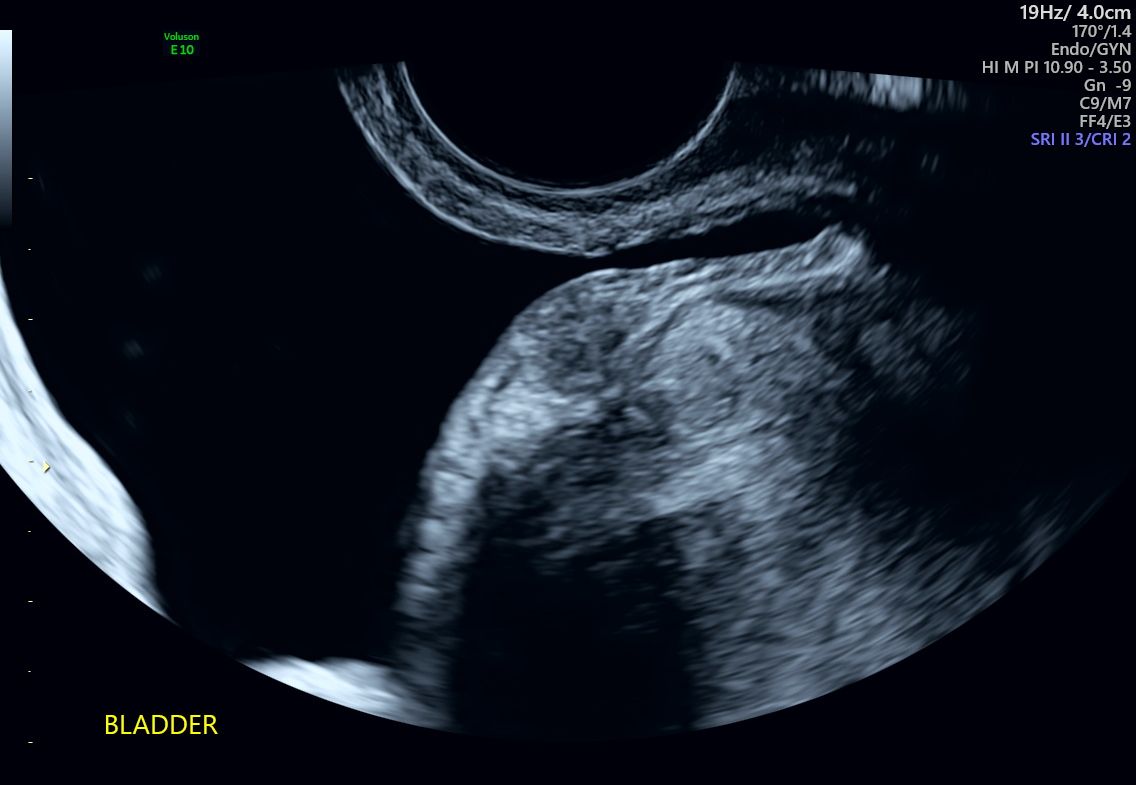

Bladder Endometriosis